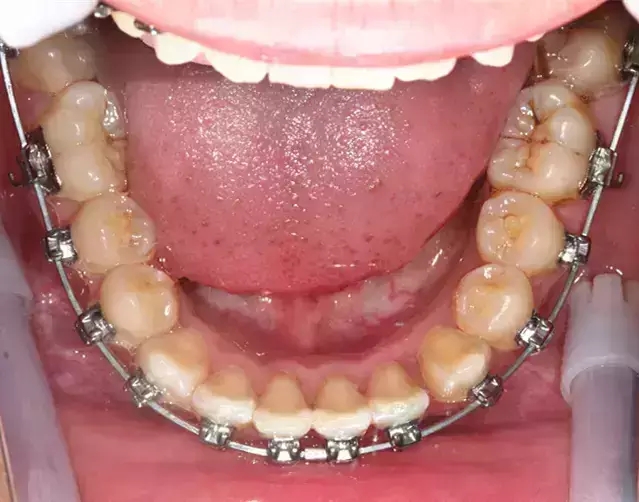

Damon 病例分享:安氏 II 類二分類露齦笑的矯治(董一磊)